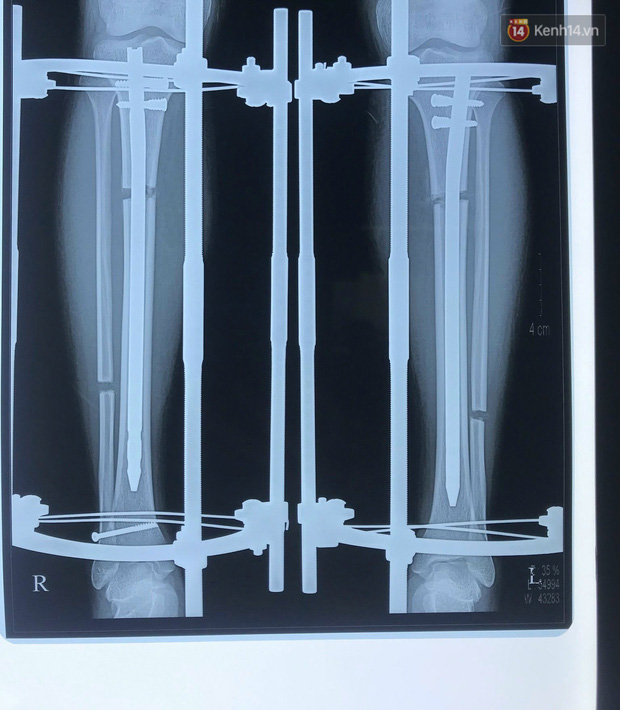

Tâm (nickname hyanna115, sinh năm 1996, sống tại Hà Nội) vừa phẫu thuật kéo chân được 30 ngày. Cô bạn có chiều cao ban đầu là 1m48 và hy vọng mình có thể cao thêm 7cm sau khi kéo chân. Mỗi ngày, Tâm kéo khung 3 lần, mỗi lần cách nhau 8 tiếng. Khung có 6 mặt, cứ 3 mặt tương ứng 1mm. Đó là một hành trình gian nan, cần tâm lý vững và chịu đau giỏi.

Đến ngày thứ 7 sau khi mổ, quá trình kéo giãn tách xương bắt đầu. Tâm tự kéo giãn chân theo chỉ định của bác sĩ: Một ngày 3 lần, mỗi ngày tăng thêm 1mm. Hiện tại, Tâm vẫn chưa biết mình có thể kéo tối đa bao nhiêu cm vì điều đó phụ thuộc vào cơ địa mỗi người. Có người kéo lên được tối đa 10,4cm, có người ít hơn.

Tâm chọn kéo khoảng 7cm vì đó là trong khoảng an toàn để cơ thể có thể hồi phục nhanh nhất và tốt nhất. Cô cũng được bác sĩ khuyến cáo rằng không đau thì cũng không được kéo giãn chân nhiều hơn 3 lần/ngày vì điều đó sẽ ảnh hưởng đến quá trình hình thành can xương.

Hiện tại, Tâm đã cao thêm 2cm. Khoảng 2 tháng nữa, cô sẽ gặp bác sĩ để tháo khung nẹp ở chân.

Quá trình kéo dài chân sẽ bao gồm 3 giai đoạn: mổ trực tiếp, kéo dài và phục hồi. Trong đó, 2 giai đoạn đầu tiên cơ thể phải chịu đựng những cơn đau cực kỳ khủng khiếp.